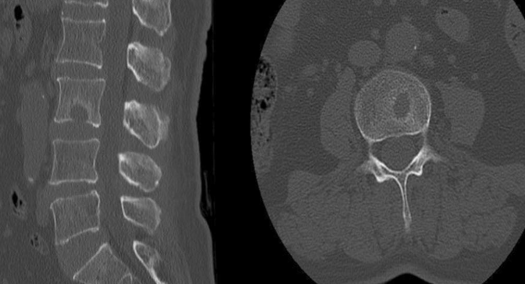

椎间盘游离 椎体内疝 椎体内疝或者说许莫氏结节(schmorl node)是指椎

许莫氏结节

许莫氏结节及终板炎影像诊断